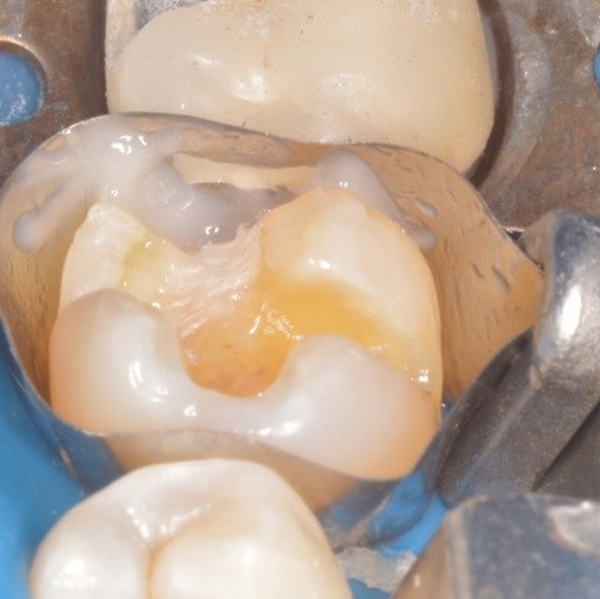

#16 Large composite by Dr. Ahmad Fayad

Posted on February 24 2018

The below case was completed and documented by our guest presenter, Dr. Ahmad Fayad. This is a great example of a Greater Curve band and technique at work! Introduction: In... Read More